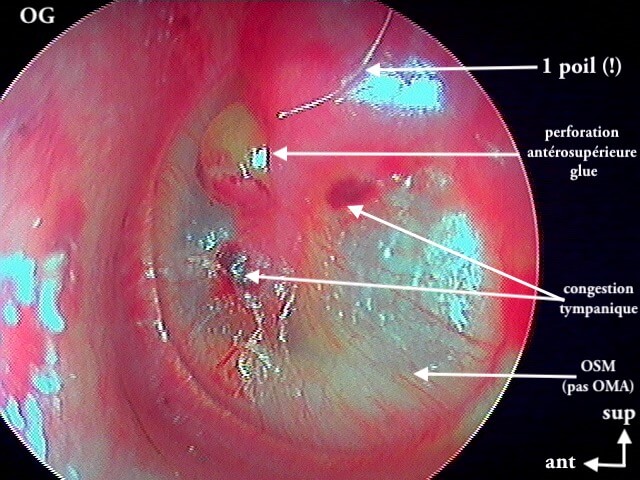

3/2 barotraumatique

– stade I : hyperhémie du manche du marteau et de la pars flaccida ;

– stade II : tympan rétracté, congestif, immobile

– stade III : aspect d'otite séromuqueuse

– stade IV : aspect otite séro-hémorragique, otohématome

– stade V : perforation

Ici des stades V perforés

Ici une otite séromuqueuse gauche perforée cicatrisée à 1 mois (cicatrice inférieure)

Une otite séromuqueuse droite perforée (et non otite moyenne aiguë)

L' aspect est difficile à voir chez les enfants (j'utilise un endoscope 0° 2,7mm de diamètre d'où la petite image): c'est finalement une otite séromuqueuse gauche perforée et non otite moyenne aiguë.